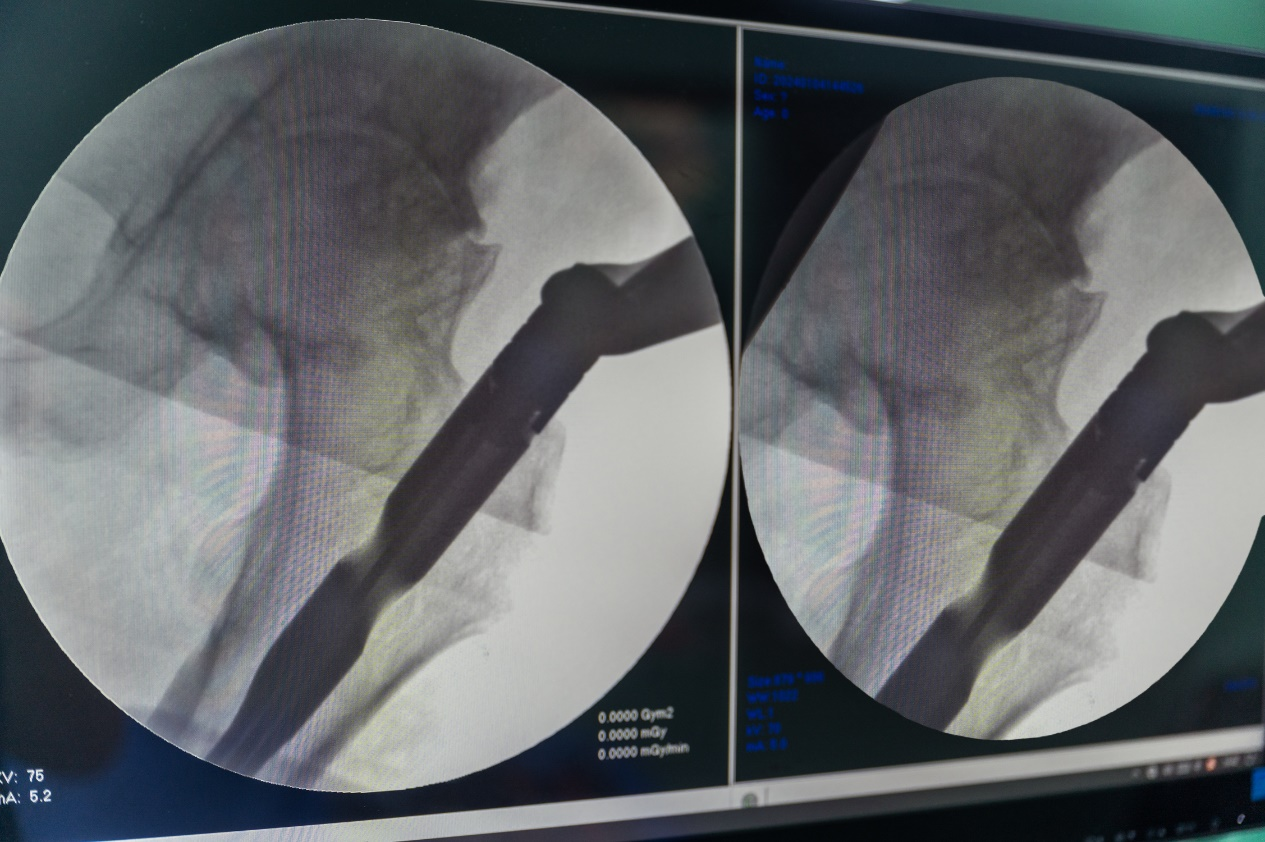

强直性脊柱炎引起髋关节间隙变窄,屈髋畸形,骨折断端移位大,复位困难。

机器人牵引复位髓内针固定

5.透视复位,观察复位情况